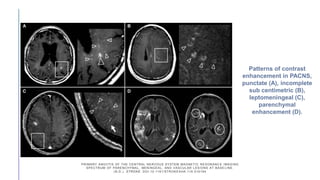

Patterns of contrast

enhancement in PACNS,

punctate (A), incomplete

sub centimetric (B),

leptomeningeal (C),

parenchymal

enhancement (D).

PRIMARY ANGIITIS OFTHE CENTRAL NERVOUS SYSTEM MAGNETIC RESONANC E IMAGING SPECTRUM OF PARENCHYMAL, MENINGEAL, AND VASCULAR LESIONS AT BASE LINE. (N.D.). STROKE. DOI:10.1161/STROKEAHA.116.016194 Patterns of contrast enhancement in PACNS, punctate (A), incomplete sub centimetric (B), leptomeningeal (C), parenchymal enhancement (D).